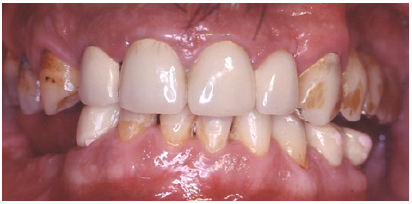

The Caucasian 53-year-old male patient was seeking treatment. His chief complaint was difficulty in chewing and his anticipation for a fixed restoration (Figure 1).

Figure 1: Preoperative intraoral frontal view.